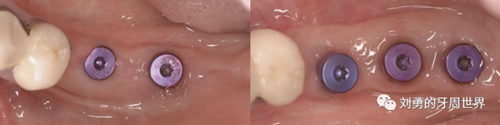

上圖中,種植體唇側(cè)缺乏附著齦,從上腭取瓣,常規(guī)做法:取長而寬的齦瓣,這樣供區(qū)面積大,術(shù)后疼痛重。

為了減少痛感,從雙側(cè)上腭取多條長而窄的齦瓣進(jìn)行移植,這樣每個供區(qū)的傷口都比較窄,可以減少術(shù)后的痛感。